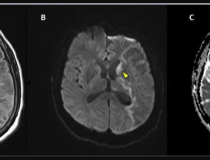

This photo gallery shows the variety of radiological presentations of COVID-19 (SARS-CoV-2) in medical imaging, including computed tomography (CT), radiograph X-rays, ultrasound, echocardiograms and magnetic resonance imaging (MRI). The radiology images show examples of typical COVID pneumonia in the lungs and the numerous complications the virus causes in the body in multiple organs, including the brain, kidneys, heart, abdomen and vascular system.

Ultrasound, especially hand-held ultrasound imaging devices, have become a primary imaging modality for novel coronavirus because of the ease to bag the device and sterilize it after use. CT and mobile X-ray systems are also used as front-line imaging systems for COVID-positive or suspected COVID patients.